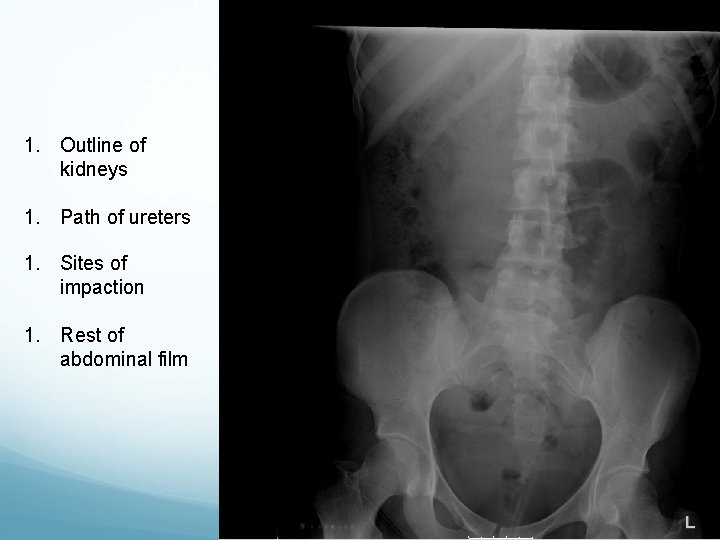

What to look for on a KUB � 90% stones are radio-opaque � Ureteric stones are sausage shaped due to peristalsis of ureters 1. Outline of kidneys 2. Path of ureters � Hila of kidneys L 1 � Tips of transverse processes � SIJ at pelvis 3. Sites of impaction � PUJ � Pelvic Brim � VUJ 4. Rest of abdominal film

1. Outline of kidneys 1. Path of ureters 1. Sites of impaction 1. Rest of abdominal film